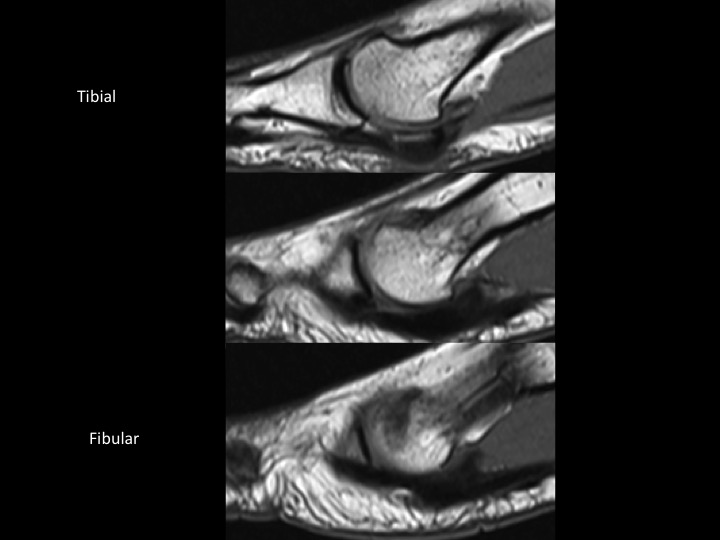

31F 5 years pain, evaluate sesamoid AVN

In the AP XR, the fibular sesamoid is not visible, but in the sesamoid view, its diminutive, smooth and not sclerotic. This leads me to believe that this is marked hypoplasia rather than AVN. Hallucal sesamoid variants are common. Aplasia is uncommon. Hypoplasia is not rare, but this degree of hypoplasia seems unusual. Based on the images, it seems there is compensatory thickening of the fibular portion of the plantar plate (sesamoids are embedded in the plantar plate). Structures stay where they are supposed to be: the tibial sesamoid is located and the FHL is midline in the short axis image. Shes had pain for 5 years....which I cannot explain, other than to say that normal variants may be symptomatic. The attached article is a little crazy, check it out. Reference article.